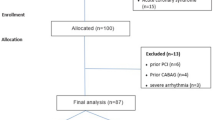

391 patients with an enhanced risk for CAD underwent coronary calcium scoring for risk stratification. All patients gave written informed content and filled out a brief questionnaire. Blood was drawn prior to the examination and stored for <4 h at 4 °C before processing. Plasma aliquots were frozen at −80 °C until assays were performed. The study was approved by the institutional ethics committee for human subjects. Arterial hypertension was defined by taking either antihypertensive drugs prescribed by a physician or reported systolic blood pressures consistently higher than 140 mmHg. Hyperlipidemia was defined by a total cholesterol >200 mg/dL or the use of statins for hyperlipidemia at present or in the past. Smoking was defined positive for all current or former smokers. Diabetes was defined by the use of antidiabetic drugs.

Two groups “High” and “Low” were built for EFV and its progression using the median. Differences across groups were tested by the independent samples Mann–Whitney U test. A multivariable logistic regression model including age, sex, cardiovascular risk factors and several cytokines binned by median was used to find independent factors for high epicardial fat volume. Non significant factors were stepwise excluded by the Wald algorithm.

For 94 patients follow-up data could be obtained after 1.9 ± 0.5 years. The overall annualized progression of CAC was at median 4 AU (IQR 0;13). High-EFV at baseline was significantly correlated with the progression of CAC. While patients with Low-EFV at baseline showed no progression of CAC, patients with High-EFV at baseline had a progression of 13 AU (IQR 2; 47) at follow-up which was statistically highly significant (P < 0.001). Regarding the annualized relative difference of EFV, associations were found for IP-10 (P = 0.049) and MCP-1 (P = 0.05) (Fig. 3).